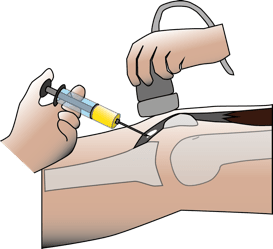

Les principales études cliniques en traumatologie du sport.

Les études sont nombreuses en traumatologie du sport, cherchant à démontrer l’efficacité des injections de PRP dans les lésions musculaires, les tendinopathies chroniques et dans de nombreuses indications chirurgicales.

La tendinopathie épicondylienne ( « tennis elbow » ou « épicondylite ») a fait l’objet de plusieurs études.

M. Bouvard et B. Eichene (Journal de Traumatologie du sport, 2014) ont retenu dans la littérature 3 études à haut niveau de preuve menées sur le tendon épicondylien (injection unique, versus corticoïdes). 2 études sur 3 ont mis en évidence une supériorité des PRP, surtout à long terme.

L’aponevrosite plantaire (inflammation sous le pied) a fait l’objet de nombreuses publications. 2 études de haut niveau de preuve, de Monto RR et de Kim E et Lee JH confirment l’efficacité du PRP dans la prise en charge des aponevrosites, supérieure aux infiltrations de corticoïdes.

La tendinopathie rotulienne est une pathologie sportive parfois invalidante pour les athlètes. Moins invasif et avec des suites courtes, le PRP peut présenter une alternative intéressante à la chirurgie dans ces tendinopathies rebelles, résistantes au traitement médical bien conduit.

3 études de haut niveau de preuve sur le tendon patellaire, confirment l’efficacité du PRP surtout à long terme.

Sur les lésions musculaires cette thérapeutique semble efficace sur le délai de reprise du sport et la récidive, à condition que ce traitement intervienne au plus tard le 9eme jour après l’accident. L’auteur reconnaît que son étude présente des faiblesses en particulier sur le nombre de patients inclus et le recul insuffisant, 4 mois à 2 ans.

Rostyslav Bubnov dans une étude à haut niveau de preuve dans le traitement des lésions musculaires aigües a obtenu des résultats encourageants en particulier sur le soulagement de la douleur et la récupération physique, en terme de délai comme de qualité.

Ce qui en fait une bonne indication dans les lésions de mauvais pronostic naturel.